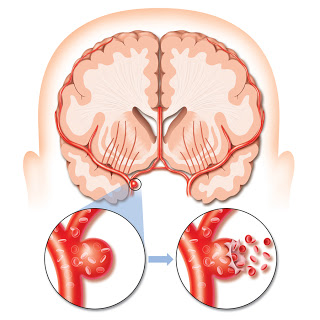

뇌경색 초기증상에 대하므로 살펴볼게요니다. 뇌에도 혈관이 있어서 피가 흐르고 있어요. 뇌에 있는 혈관이 막혀서 뇌의 일부가 손상되는 것을 뇌경색이라고 말해요. 뇌혈관이 막혀 뇌가 손상되면 장애가 발생할수 도 있으므로 뇌 연관 질환은 각별한 주의가 필요해요.

뇌경색의 주된 이유가 되는 것은 혈전이지요. 혈전이란 혈관 속에 피가 굳어진 덩어리를 얘기하는데 이것이 혈관을 막는 것이 뇌경색에 큰 영향을 줄 수 있습니다. 평균적으로 많이 발생하는 연령대는 5~60대이지요. 뇌경색은 양쪽 뇌에 모두 나타나는는 것이 아니라 주로 한쪽 뇌에만 발생하지만, 주로 한쪽 팔다리가 마비되었다거나 얼굴 근육이 굳어버리기도 해요. 그렇기에 뇌경색 초기증상이 발생한다면 민첩하게 대응를 해야 하겠습니다.

또 뇌경색의 까닭은 혈관의 협착을 유발시키는 동맥경화증이고요. 동양에서는 뇌내동맥경화증이, 서양에서는 경동맥동맥경화증이 많이 나타나고다. 그리고 흡연, 고지혈증, 당뇨병, 고혈압, 건강에 옳지 않은 식습관, 스트레스 등도 뇌경색을 발생시키는 위험요인입니다.모든 질병에 단일 이유가 되는 것이 없듯이 뇌경색도 단일 이유가 되는 것이 아닐 수 있고요.